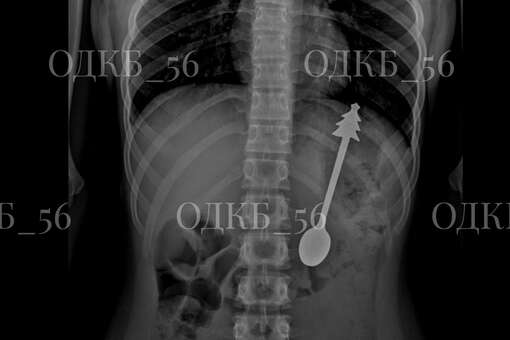

По данным ведомства, несовершеннолетний случайно проглотил ложку, после чего его срочно госпитализировали. Бригада скорой помощи доставила ребенка в детскую больницу, где ему сделали рентген органов брюшной полости. В результате выяснилось, что инородное тело находится в желудке.

«В экстренном порядке проведено <...> эндоскопическое удаление инородного предмета — металлической ложки длиной 14 см. Постманипуляционный период протекал без осложнений», — говорится в заявлении.

Публикация дополнена фотографиями извлеченной из ребенка ложки. На кадрах видно, что на конце ручки столового прибора находится фигурка елки.